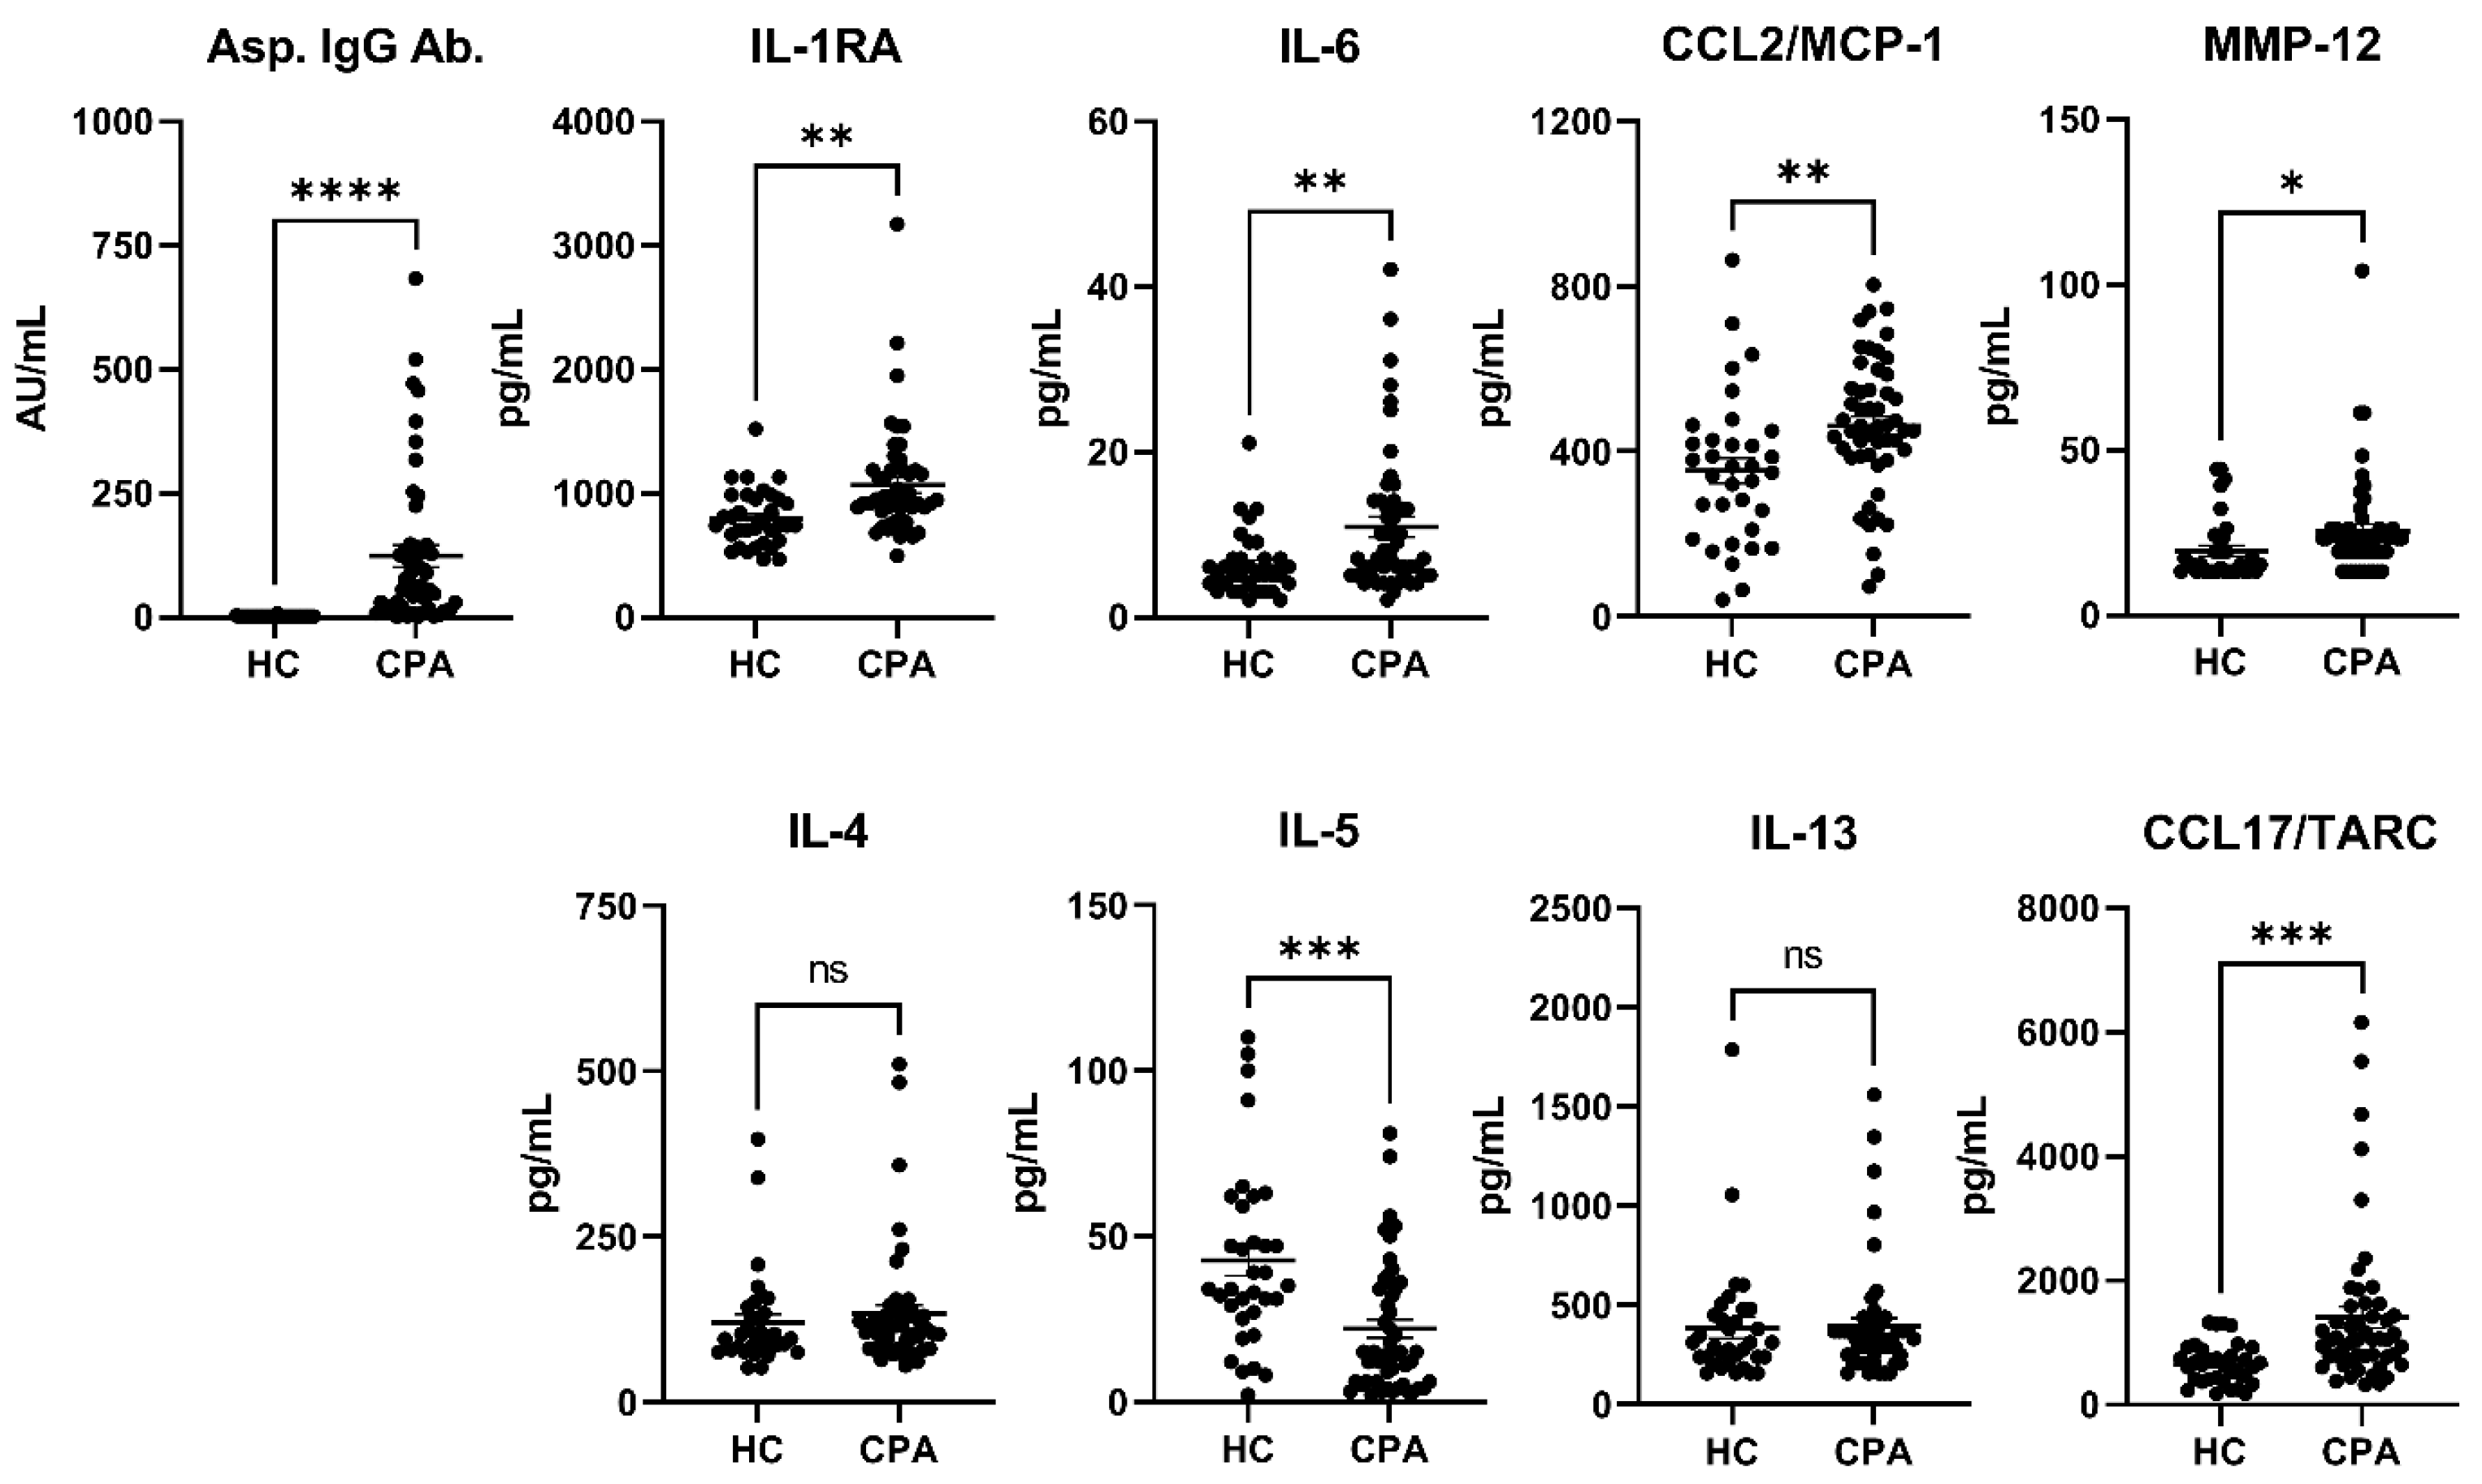

3.2. Cytokines (HCs vs. CPA)

| Asp. IgG Ab. (AU/mL) | 0.4 ± 1.1 | 205.3 ± 598.5 | <0.0001 | **** |

| IL-1RA | 794 ± 230.3 | 1067 ± 443.7 | 0.0014 | ** |

| IL-4 | 120.4 ± 72.4 | 133.7 ± 90.7 | 0.48 | |

| IL-5 | 42.7 ± 27.4 | 22 ± 19.7 | 0.0001 | *** |

| IL-6 | 6.2 ± 3.9 | 11 ± 8.8 | 0.0041 | ** |

| IL-13 | 384.9 ± 306.7 | 395.2 ± 287.1 | 0.88 | |

| CCL2/MCP-1 | 353 ± 180.3 | 461.9 ± 162.9 | 0.0049 | ** |

| CCL17/TARC | 651.1 ± 330.2 | 1410 ± 1247 | 0.0009 | *** |

| MMP-12 | 19.5 ± 9.5 | 25.5 ± 15.5 | 0.049 | * |